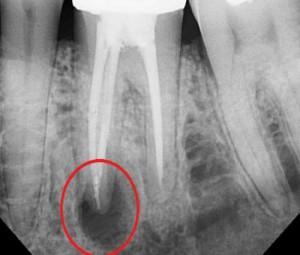

Если воспалился корень зуба давно и боль распространилась на соседние жевательные органы, локализацию очага определяют с помощью рентгена. Стандартная тактика предусматривает удаление кариозных поражений. При глубоком проникновении кариеса зуб депульпируют.

Через 2-3 дня в повторно промытые корневые каналы закладывают препараты пролонгированного воздействия и ставят временные пломбы (рекомендуем прочитать: ). При прекращении образования гноя зуб пломбируют постоянным составом. Для оценки результатов лечения воспаления десны и корня зуба используют рентген (рекомендуем прочитать: ).